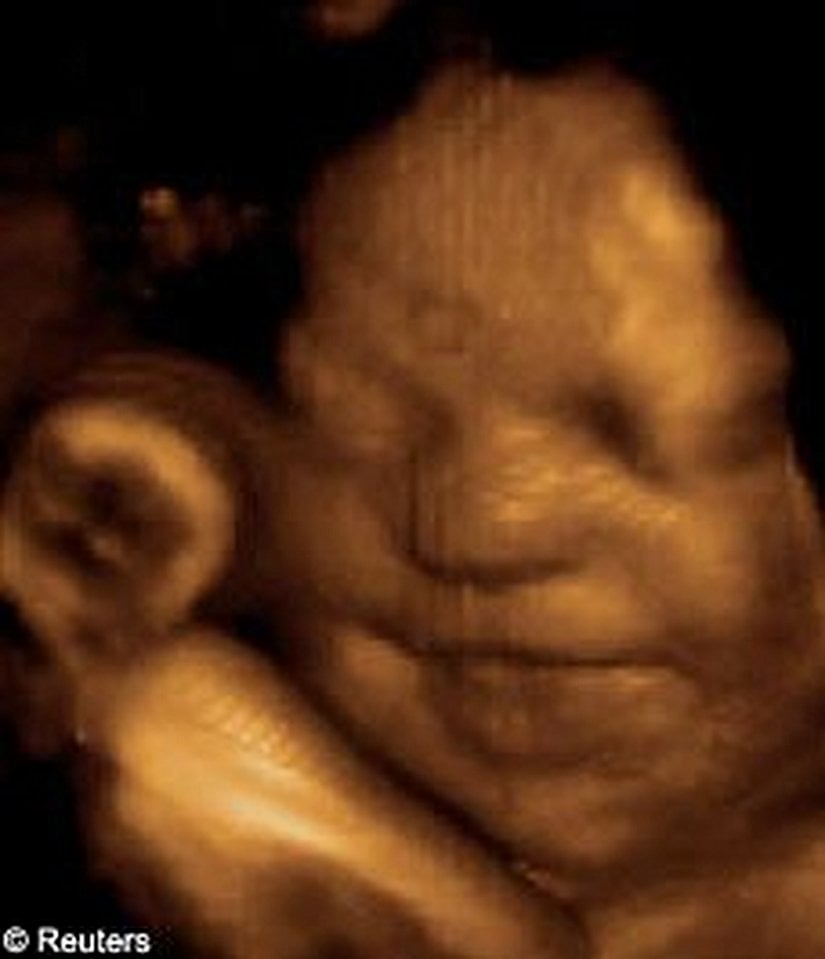

Ama giderek popülerleşen bir teknoloji sayesinde ebeveynler artık yavrularını çok daha net görebiliyorlar: 3D ve hatta 4D ultrason! Monako'daki Princes Grace Hastanesi'nde görev yapan Dr. Bernard Benoit, uzun yıllardır 3 boyutlu (ve hatta 4 boyutlu) ultrason görüntüleme teknikleri üzerinde çalışıyor ve çok başarılı sonuçlara da imza atmış vaziyette. Aşağıda, bunun bir örneğini görüyorsunuz.

Bu görüntüleme tekniği sayesinde, artık renkli ve çok daha net sonuçlara ulaşabiliyoruz. Bu görseller, bunun en net ispatlarından biri. Ana karnındaki ikizleri çok detaylı bir şekilde görüntülemek artık mümkün. Hem de o, uzaktan odaklanılmış bir kare. Aşağıdakiler, ne demek istediğimizi daha net anlatacaktır:

3D ultrasonlarda, birden fazla açıdan 2 boyutlu görüntüler çekiliyor ve sonrasında bilgisayar yardımıyla 3 boyutlu bir görsele dönüştürülüyor. Bu sayede bebeğinizin sadece bir kesidini değil, 3 boyutlu bir görüntüsünü elde etmeniz mümkün oluyor.

4D ultrasonlarda ise, 3D olan görüntüler zamana yayılmış bir şekilde kaydediliyor. Bu sayede bebeğin hareketlerini tıpkı bir video izler gibi görmeniz mümkün oluyor. Bu sayede bebeğin gözlerini açıp kapaması, gülümsemesi veya parmağını emmesi gibi olayları çok net bir şekilde görüntüleyebiliyorsunuz.